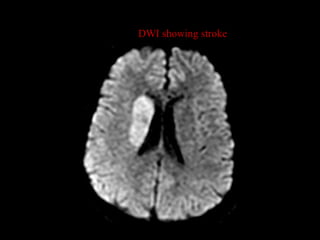

DWI showing stroke

• #41 New strokes usually show up as white on T2.